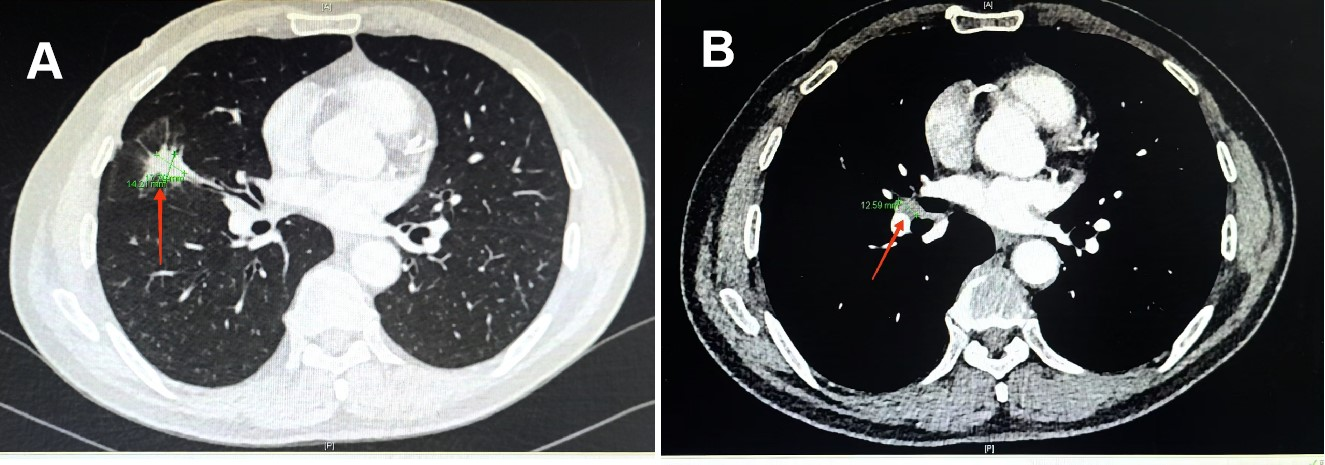

图2 向先生治疗前的CT,原发肿瘤近4cm(见图A红色箭头)和肺门转移淋巴结(见图B红色箭头)

“医生,如果我只接受放化疗,病情会不会复发?”向先生及家人不停的询问医生。小细胞肺癌放化疗后病情复发,这是患者和医生共同的担心,如何有效延长小细胞肺癌放化疗后复发时间,甚至降低其复发率。针对这一临床难题,徐智主任带领的团队开展了一项多中心临床研究:斯鲁利单抗联合依托泊苷+卡铂化疗在IIb-IIIb期小细胞肺癌新辅助治疗中的疗效及安全性研究。 针对向先生的担心,徐智教授医疗团队耐心地与他及家属沟通,最终向先生自愿加入这个研究项目。随后治疗团队根据研究方案为向先生实施了化疗联合斯鲁利单抗免疫治疗,旨在缩小肿瘤大小、减少肿瘤淋巴结转移,把IIIA期小细胞肺癌转化为IIA期甚至更早期,为向先生争取手术机会。值得一提的是向先生使用的斯鲁利单抗由课题组免费提供。 经过4个周期的治疗,向先生的肺部病灶显著缩小,肺门淋巴结也明显缩小(见图3),整个治疗过程中也没有发生明显的不良反应。经过医院MDT(多学科团队协作)会诊,向先生的小细胞肺癌分期成功由IIIA期降至IIA期,大家一致认为已达到手术条件和要求。8月23日新桥医院胸外科在全麻下为向先生做了肺癌根治性切除手术。手术过程顺利,术后的病理结果显示切除的病灶和淋巴结中没有发现肺癌细胞,达到了病理完全缓解(PCR)(见图4)。向先生术后恢复良好,精神状态和气色俱佳,5天后高兴地出院回家。 图3 经过4周期治疗后肺部原发病灶明显缩小(见图A红色箭头)和肺门淋巴结明显缩小(见图B红色箭头) 对于向先生治疗的成功,新桥医院呼吸与危重症医学中心主任徐智教授详细解释道,根据目前临床诊疗规范,类似向先生这样的IIB-IIIB期的小细胞肺癌患者没有机会接受手术治疗,也无法接受目前先进的肿瘤免疫治疗,存在未被满足的临床治疗需求。而采用化疗与免疫治疗联合治疗是将目前最先进的治疗方案用于这类患者,并且尽量为其创造根治性手术切除机会。当然,这一方案是否能显著延长这类小细胞肺癌患者的复发时间、降低复发率,让患者有高质量的长生存时间还有待科学系统的临床研究。徐智教授的这项研究正在入组患者,欢迎有需求的患者来院咨询。